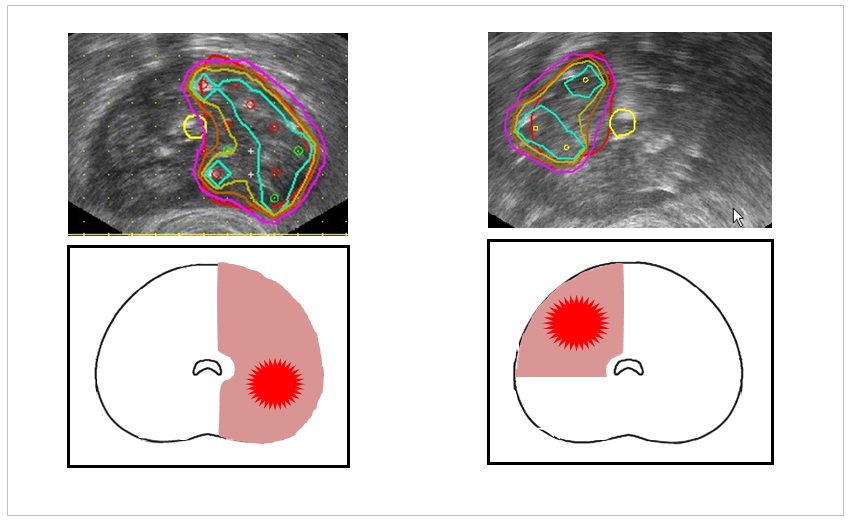

さらに最近では、この手法を用いることで、よりがん領域に絞った部分治療もできるようになってきたという。部分治療導入当初は、尿道を真ん中として、前立腺の片側半分の2分の1領域の治療を行っていたが、現在では前立腺を4分割で評価することができ、4分の1領域での部分治療にも取り組んでいるそうだ。

「基本的に部分治療では、尿道を中心に左右に分けて半分の領域を治療するのですが、最近ではさらに治療域を小さくして、尿道を軸に左右と前後(腹側、背中側)の4分の1の領域に分けて生検を行い、治療をしています」(図4)

よりがん領域に絞った部分治療も可能になってきているのだ。